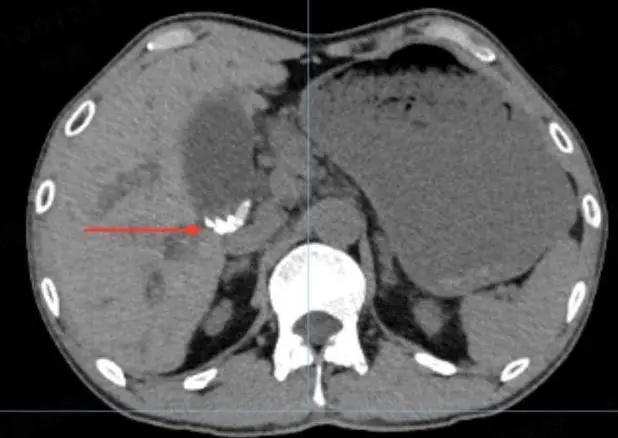

全腹CT提示:

胆囊内团簇高密度影

胆总管下段与肝内也存在高密度影

疑似胆总管结石,胆囊结石

(腹部CT“肝吸虫”,疑似“虫卵或死虫”)